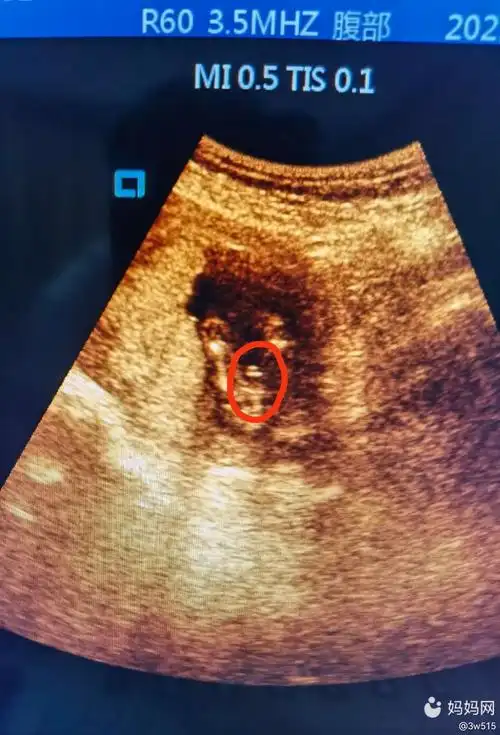

18周的胎儿

孕18周 5天中山市8月31日 2 6